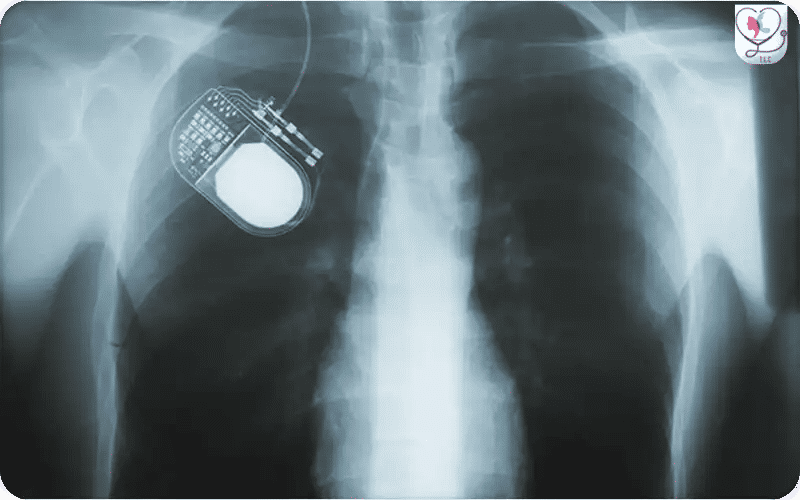

X-ray view of a Deep Brain Stimulation (DBS) system showing the pulse generator implanted in the chest. The extension wire travels up the neck and connects to the intracranial electrodes, providing a detailed technical perspective of the full hardware configuration within the patient.

During the Deep Brain Stimulation (DBS) procedure, the pulse generator—a small, battery-powered device—is implanted under the skin, usually in the upper chest area. This device connects to the electrodes placed in the brain via a thin extension wire, enabling controlled electrical stimulation to manage neurological symptoms.